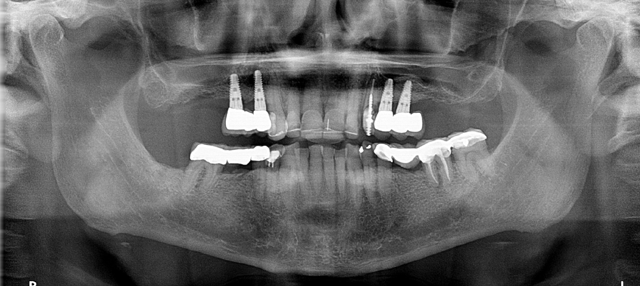

Fig. 1 Fig. 2

A CBCT scan was taken with a Carestream Dental CS 9300 (Figs. 2 and 3) and an intraoral scan was obtained using a Carestream Dental intraoral scanner (Figs. 4 and 5).

Fig. 3 Fig. 4